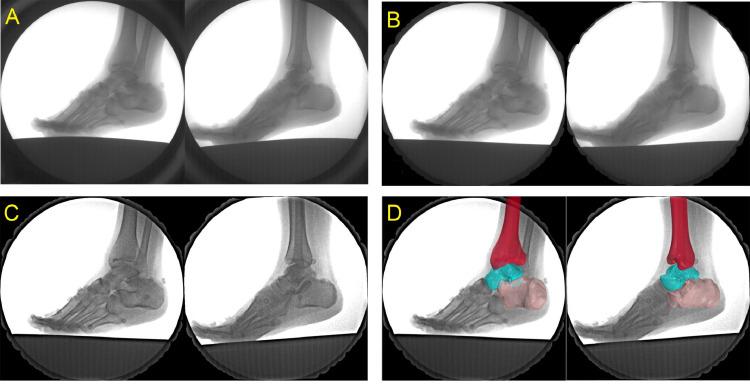

Fifteen healthy male recreational runners underwent foot computed tomography scanning for the construction of 3-dimensional models. A high-speed DFIS (100 Hz) was used to collect 6 degrees of freedom kinematics for participants' tibiotalar and subtalar joints when they adopted RFS and FFS in barefoot condition.

Foot kinematics, such as excessive eversion and malalignment of the hindfoot, are believed to be associated with running-related injuries. The majority of studies to date show that different foot strike patterns influence these specific foot and ankle kinematics. However, technical deficiencies in traditional motion capture approaches limit knowledge of in vivo joint kinematics with respect to rearfoot and forefoot strike patterns (RFS and FFS, respectively). This study uses a high-speed dual fluoroscopic imaging system (DFIS) to determine the effects of different foot strike patterns on 3D in vivo tibiotalar and subtalar joints kinematics.